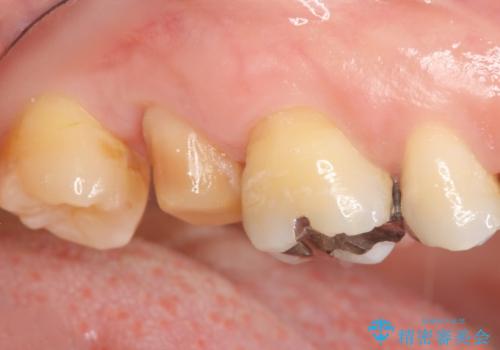

- 奥歯に違和感があることを主訴に来院された患者様です。

精査したところ、右上の奥歯(右上7)はう蝕が深く骨吸収も進行しており保存不可能な状態でした。

金属アレルギーの疑いがあり、インプラントも避けたいとの患者様のご希望により、親知らずを移植することにしました。